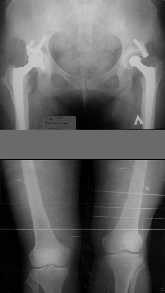

Женщина, 29 лет.В 2001 году получила политравму (таз, открытый многооскольчатый перелом правой бедренной кости на границе средней и нижней трети со смещением,

открытый перелом правой голени, пятки, закрытый - правого надколенника, поперечного отростка L4, пальцев кисти, сотрясение головного мозга).

Переломы конечностей лечились АВФ.В настоящее время стойкая разгибательная контрактура правого коленного сустава (сгибание 105-110 гр., разгибание 160-165 гр.), варусная деформация, болевой синдром.

Вопросы: 1.Определение уровня корригирующей остеотомии для устранения варусной деформации правой нижней конечности (остеотомия на бедре или голени)?

2. Рекомендации по оперативному пособию для устранения посттравматической варусной деформации правой нижней конечности?

Даже по этим коротким снимкам видно, что варусная деформация на уровне бедра. Хотя для полноценной оценки оси сделать надо снимок всей конечности, от таза до стопы. Наклеить метки на кожу, по которым сделать склейку. И профиль бы тоже неплохо посмотреть.

Уважаемый Антон, при определении уровня остеотомии и величины коррекции руководствуемся, обычно, необходимостью обеспечить нормаль механической оси к середине опорной поверхности большеберцовой кости. Расчет производится по рентгенограмме (рентгенограммам) конечности под нагрузкой, которые визуализируют положение головки бедренной кости относительно таранной кости. На представленных рентгенограммах определить эти реперные точки (и заслужить Вашу зараннюю благодарность) не представляется возможным. Остается неясным с каким исходом сросся перелом правой большеберцовой кости. Складывается впечатление, что нанесены не механические, а анатомические оси. Исправлять проще за счет "минус - кость", но механически правильнее "плюс". Чтобы выполнить механические требования, иногда на ряду с угловой коррекцией (деваризация-экстензия, т.к. имеется не только разгибательная, но и сгибательная контрактура)необходимо медиолатеральное смещение.

имеется S-образная деформация бедра на фоне "многооскольчатого

перелома правой бедреннойљ кости на границе средней и нижней трети со смещением"

Уважаемый Антон, видимо перелом большеберцовой кости на механическую ось не повлиял, но явно варусная деформация усугубляется повреждением наружного связочного аппарата (МКС.... Просится поднагрузочный R-снимок конечности и корригировать, на мой взгляд, надо бедро (+ остеотомия, если планируется мобилизация коленного сустава).